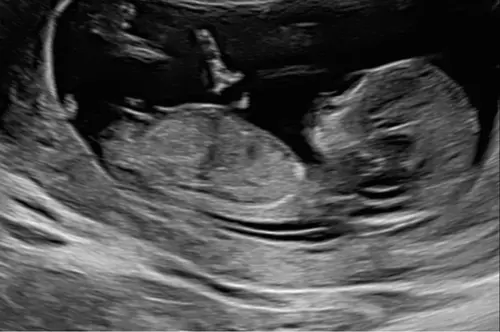

Gisteren echo en nip test gehad 12w6. Wat denken jullie?😍

Meisje inderdaad 🙃